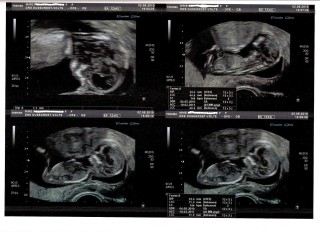

4Dです!こんなによく分かるエコー写真に感動しました!旦那もとてもびっくりしてました!愛おしいです!!

写真には12w2dと書いてありますが、予定日からの計算では12w5dです。 サイズは56.26ミリ。

動いてる姿を見て感動しました。角度によって指の形もなんとなくわかってビックリしました。

風邪を引いてしまい不安だったのですが、手や足をグイグイと動かしていました。とても元気な姿を見せてくれました。

6.7cmになりました。

初4Dでは、ちっちゃな左肩も見えて、よりいとおしくなりました♪